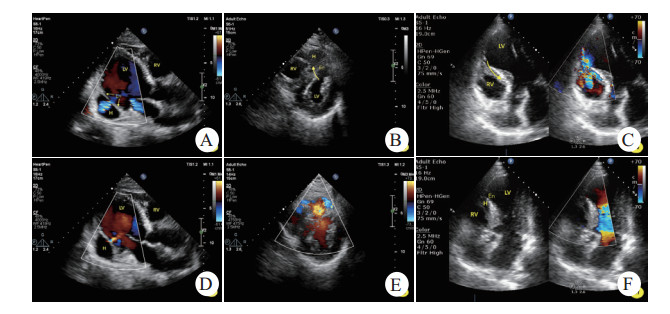

1.1 病例1男,69岁,胸痛6 d,急诊查体发现心尖区Ⅲ/6级收缩期杂音,心电图提示“下壁、后壁导联ST段上抬”,当日床旁超声心动图提示“左室下后壁运动异常,心包腔少-中量积液”,未发现穿孔或夹层。收入CCU后杂音持续存在,次日申请超声会诊,提示“左室后壁中间段心肌夹层(夹层瘤大小1.8 cm×1.6 cm)”(见图 1-A, B),同日左心声学造影证实上述诊断。临床给予药物治疗。住院第13天复查床边超声发现夹层瘤较前增大(3.3 cm×2.8 cm);第24天左心声学造影发现夹层瘤处心外膜断裂,假性室壁瘤形成,心包积液增多。会诊无外科手术指征,介入亦对预后改善不详,继续以内科保守治疗为宜。30 d病情好转出院。6个月后门诊复查超声提示“左室下后壁心肌夹层假腔内血栓形成(4.4 cm×3.4 cm)”。

| A.左室后壁心肌内夹层血肿,内膜分离清晰可见,而心外膜完整,收缩期左室血流通过交通孔进入血肿内;B.舒张期血流再经交通孔返回左室;C.心尖肌层内血肿,内膜呈不规则断裂;D.左室血流涌入血肿并与右室交通,心肌交通路径非同水平;E.室间隔内匍匐状夹层瘤,左室面见断裂的心内膜,收缩期左室血流进入夹层瘤并再次破入右室;F.舒张期夹层瘤腔隙变小。LV.左室,RV.右室,H.夹层血肿/夹层瘤,En.心内膜 图 1 不同部位心肌夹层超声表现 |

男,69岁,胸痛7 d,急诊查体发现胸骨左缘第4~5肋间4/6级连续性杂音,心电图提示“V1~4导联ST段抬高”,床边超声心动图提示“前间隔、左室前壁运动异常,左室心尖夹层瘤(2.5 cm×1.4 cm)形成并室间隔穿孔(非夹层水平)”(见图 1-C, D),临床治疗上给予药物治疗为主。1周后全麻下行室间隔封堵术,封堵未成功,术后患者血压进行性下降,一周后出现心源性休克,抢救无效死亡。

1.3 病例3男,70岁,胸痛2 d,急诊查体发现胸骨左缘第2肋间3~4级性质粗糙的收缩期杂音,心电图提示“前间壁相关导联ST段升高”,床旁超声心动图提示“前间隔、左室前壁运动异常并心尖部室壁瘤形成,室间隔穿孔并夹层,心包腔少量积液”(见图 1-E, F)。该患者放弃治疗。

2.2 超声表现及诊断思路心肌夹层通常有以下超声表现[20, 22]:①心肌梗死部位新发的不规则无回声腔,内径可随心动周期变化(收缩期增大,舒张期反之);②腔隙可见心内膜飘动,但心外膜完整;③夹层在室间隔时可见螺旋形通道;④左室与夹层瘤之间通过破口有血流交通;⑤随访可见夹层瘤内由血栓充填而自愈;⑥可合并其他心脏破裂表现,如心包腔积液[18]、乳头肌断裂、室间隔穿孔、假性室壁瘤等。Barrón等[13]指出满足以上3条及以上即可诊断心肌夹层,本研究3例均符合第①、②条表现,2例室间隔夹层见螺旋形通道(第③条),1例下后壁夹层可见夹层瘤内往返血流(第④条)以及6个月后血栓充填(第⑤条),合并症中2例伴心包腔积液、2例穿孔、1例出现晚发假性室壁瘤。